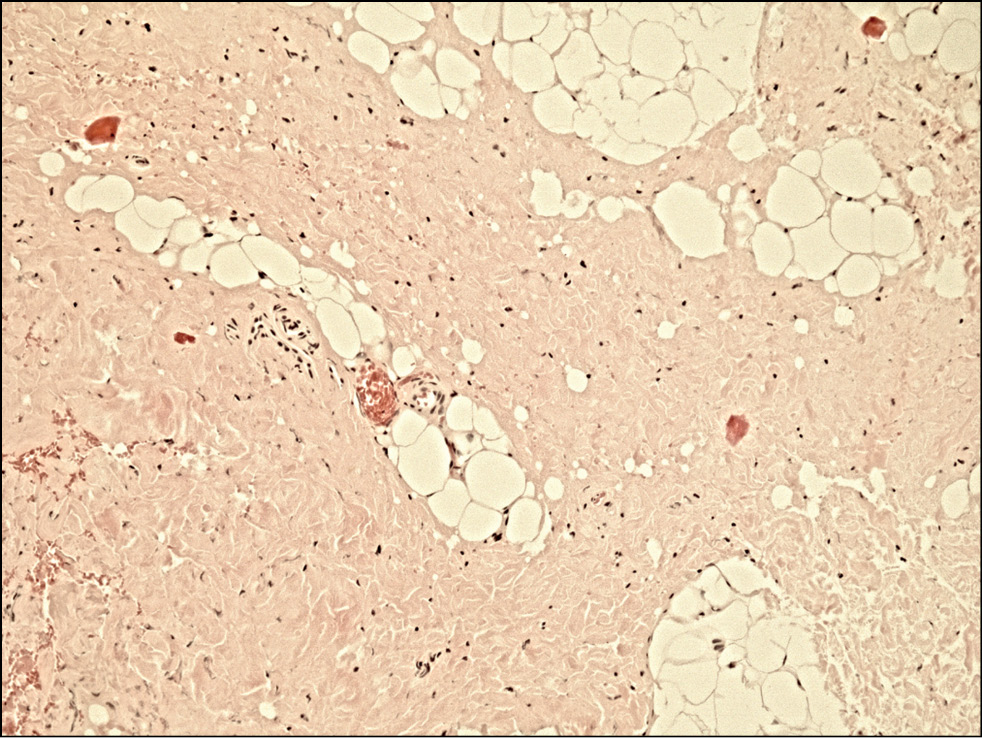

Исследование 11 фрагментов, резецированных во время операции по устранению приобретённого птоза, показало, что для 7 фрагментов характерно разрастание фиброзно-жировой ткани в виде пучков с новообразованными полнокровными сосудами, мышечные элементы в материале не дифференцировались, либо определялась выраженная белковая дистрофия. Выявляли признаки отёка и гиперплазии (рис. 6).

Рис. 6. Гистологический препарат леватора при приобретённом птозе верхнего века с разрастанием фиброзно-жировой ткани Окраска — гематоксилин/эозин, увеличение 100х.